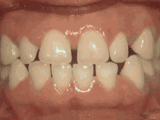

第一種

前牙移位,因?yàn)橛醒例X缺失,導(dǎo)致相鄰牙齒開始沒有秩序的前突,經(jīng)過矯正后是這樣的~